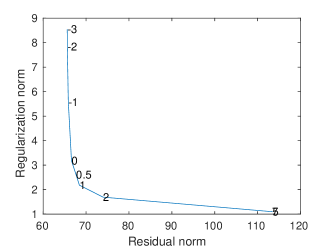

A regularization parameter common to all the PC components is chosen by inspecting the plot of the regularity of the first PC covariance functions () versus the residual norm, for different choices of the parameter. This is a version of the L-curve plot (Hansen, 2000) and is shown on the left panel of Figure B.2. Here we show the results for , in the appendices we show the results for . The energy maps of the estimated , and resulting from the analysis are shown in Figure 11. These are associated with the first three PC covariance functions , and . High intensity areas, in yellow, indicate which areas present high average interconnectivity, either by means of positive or negative correlation in time.

In Figure B.2 we show the L-curve plots associated with the PC covariance models applied to the dynamic and multi-subject functional connectivity studies.